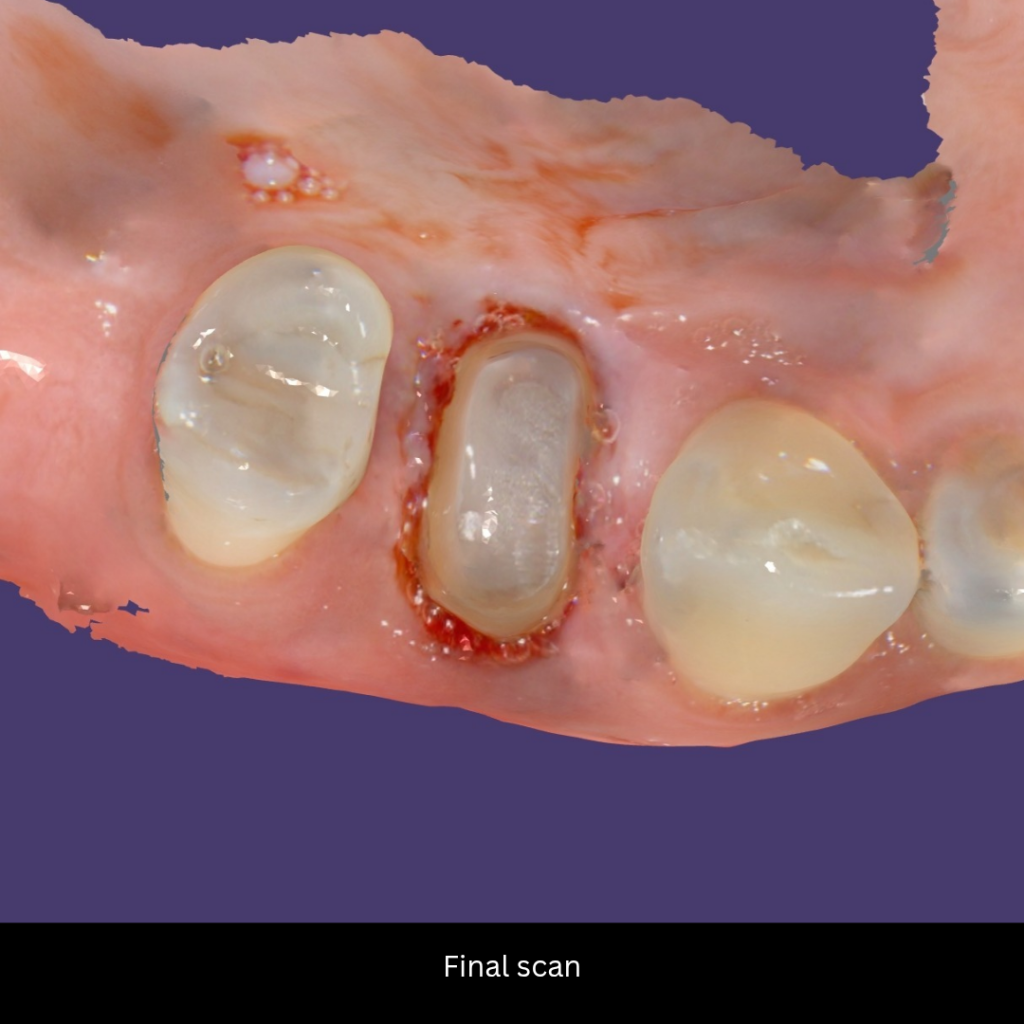

Final Scan: After the healing period, the provisional was removed, and the final impression was captured using an Intraoral Scanner

final scan